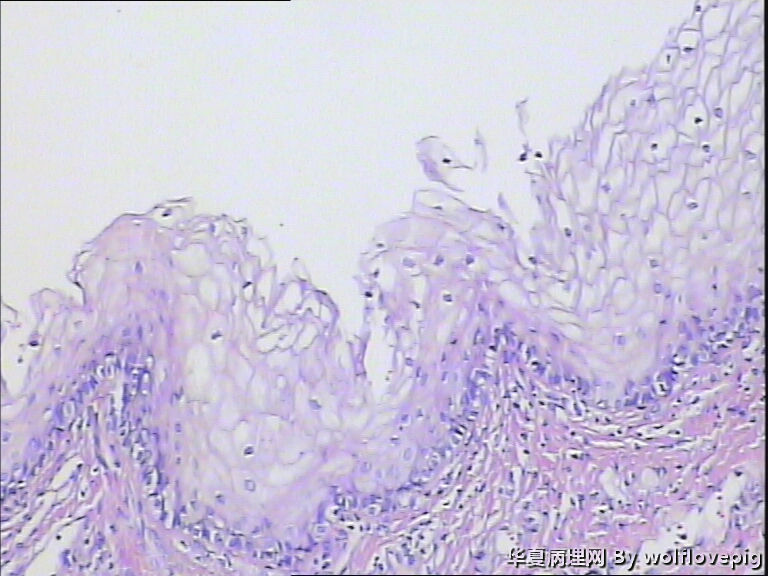

31y,阴蒂附近囊肿2.0*1.5cm

外阴最常见的囊肿是前庭大腺囊肿,囊肿一般衬以移行上皮,常伴有非角化性鳞状化生,也有的呈扁平或立方状,囊肿周边附近可以见到黏液腺体。

此例有点特殊,看到一些纤毛柱状上皮被覆,称为纤毛囊肿,属于前庭大腺囊肿的特殊改变。

前庭大腺囊肿位于外阴后半部,而此例位于阴蒂附近。

泌尿生殖窦起源的外阴囊肿(粘液性和纤毛囊肿)

1,多见于21-30及31-40的多产妇女,病变多位于外阴前庭。

2,组织学上,粘液性囊肿含有与宫颈内膜或阴道腺病一样的粘液性上皮内衬,少数情况下可出现鳞状上皮化生。也有报道有些病例出现纤毛细胞,可以与粘液上皮混合存在。